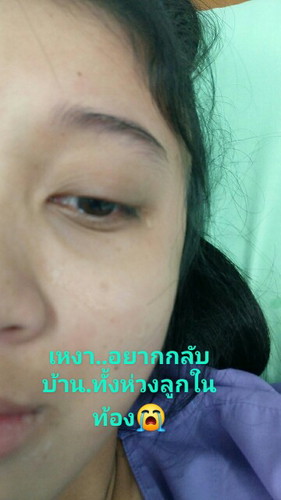

ปวดหัว.เครียด.ขอระบ่ายหน่อยนะค่ะ??

ตอนนี้ท้องได34สัปดาห์แล้ว.หมอนัดคลอด19เมษา63..แต่หมอบอกว่าเจ้าตัวน้อยเอาหัวลงพร้อมคลอดแต่ตอนนี้หมอให้คลอดยังไม่ได้.เพราะเจ้าตัวน้อยปอดไม่สมบูรณ์ หัวใจเจ้าตัวน้อยก็เต้นช้าบ้างเร็วบ้าง.หมอบอกว่าถ้าคลอดก่อนกำหนด น้องจะหายใจเองลำบากมาก.ทำไมเจ้าตัวน้อยต้องเจอเรื่องแย่ๆแบบนี้ด้วย????